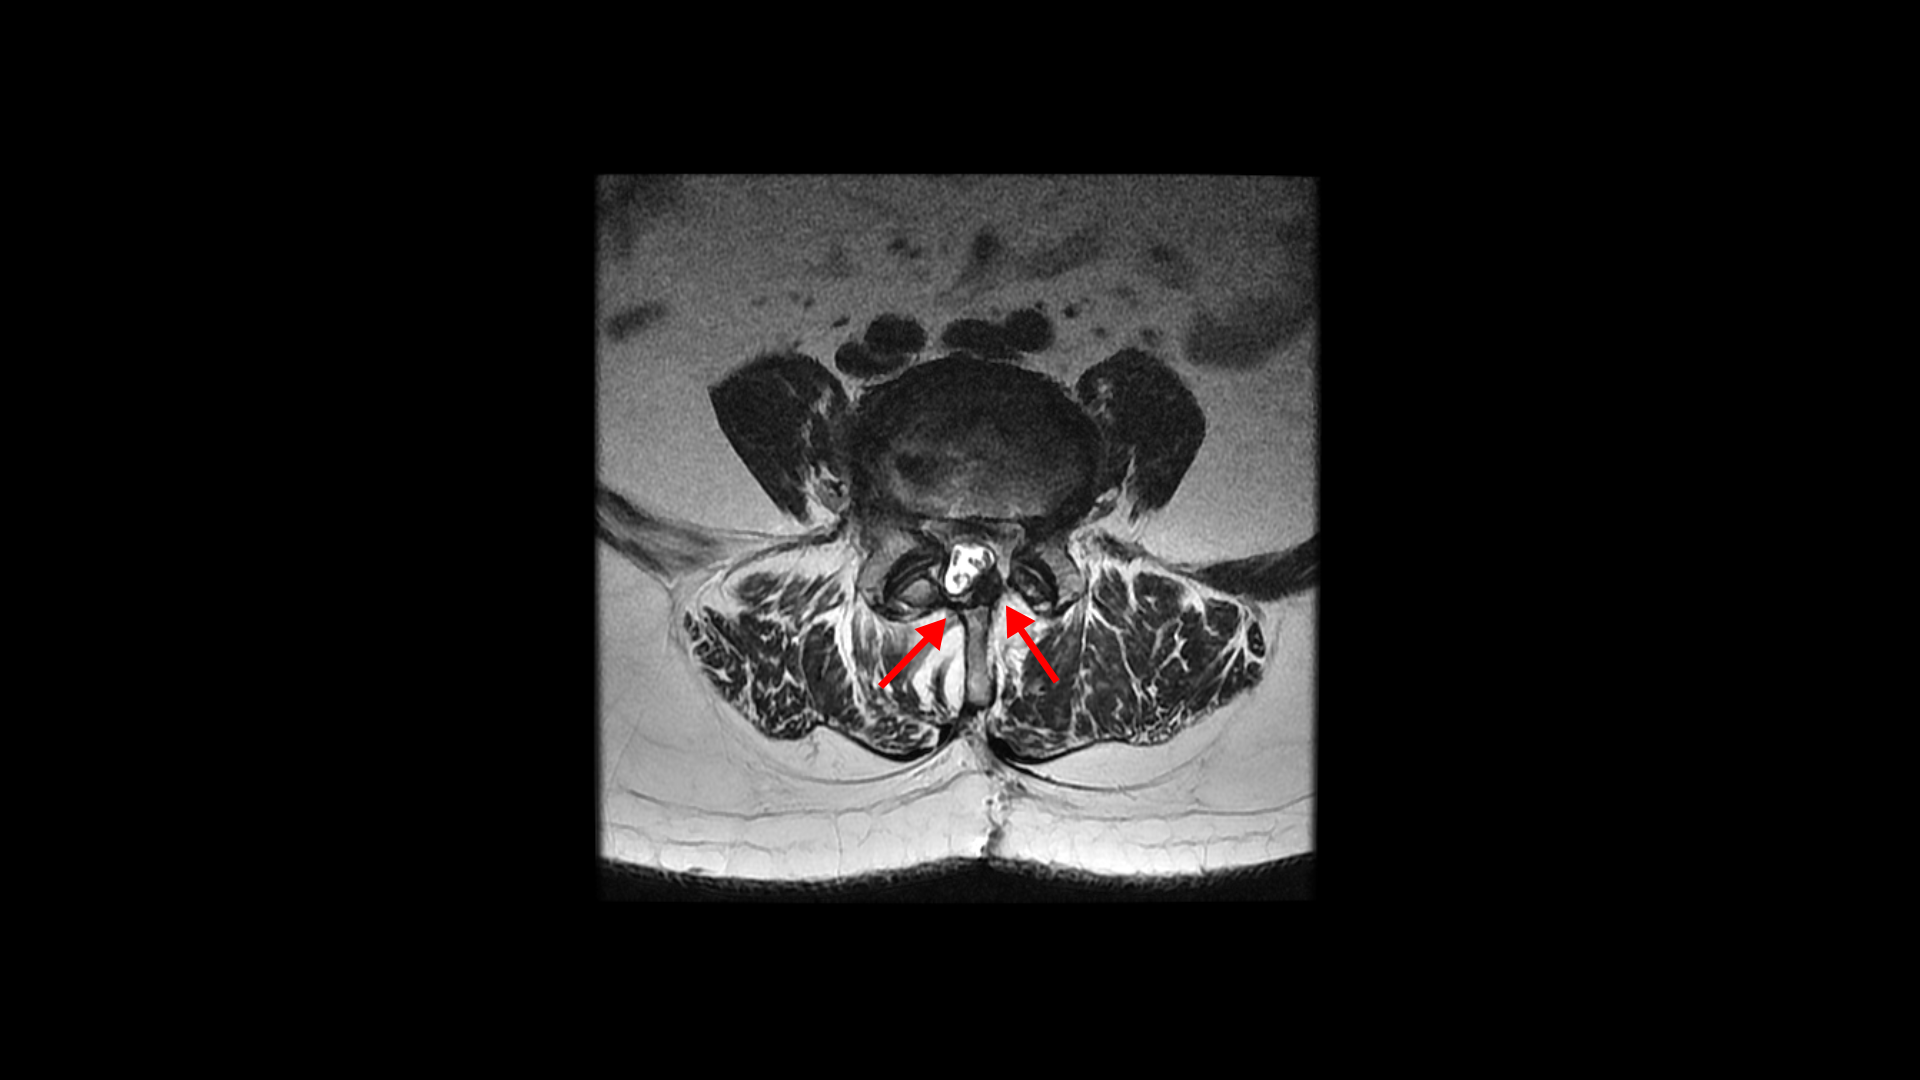

이 환자분은 허리수술을 여러 번 한 상태에서 결국에는 척추유합술까지 하셨습니다. MRI를 보시면 5번 1번 후궁에 수술한 자국이 보입니다.

4번 5번 후궁 양쪽으로 수술한 자국이 보입니다.

올해 초에 4번 5번 디스크가 또 오른쪽으로 심하게 파열돼서 결국 후궁과 후관절, 황색인대를 모두 다 제거하고 나사를 박는 척추유합술을 하셨습니다.

그런데 척추유합술을 하고 난 후 오른쪽 다리의 증상은 호전되었으나 상대적으로 증상이 괜찮았던 왼쪽 다리에 심한 방사통과 마비 증상을 호소하셨습니다. 수술한 병원의 집도의로부터 수술은 잘 됐으나 수술한 자리가 부어있기 때문에 신경을 눌러서 그런 거라고 1년 이상 기다리면 회복될 것이라는 얘기를 들으셨다고 합니다.